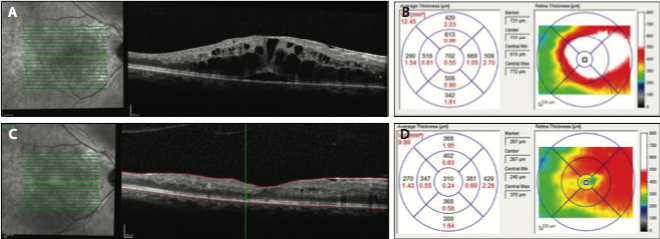

Figure 3. OCT in an eye with DME showing significant intraretinal and subretinal fluid (A). The corresponding OCT map shows increased retinal thickening (B). One month later, following an anti-VEGF injection, there was decreased intraretinal fluid and resolution of the subretinal fluid (C), as well as significant improvement in the thickness on the OCT map (D).

In patients with diabetes, OCT is clinically utilized most frequently in those with DME. This objective test has software that is capable of automatically measuring retinal thickness in multiple areas of the macula. The measurements can then be compared to large normative databases. The OCT scan can also be repeated at follow-up visits with accuracy, which is useful for assessing response to treatment over time (Figure 3).26,27

In patients with DME, OCT can show whether the macular edema is center-involving or non–center-involving. This is an important distinction in the age of anti-VEGF therapy, as these agents have frequently been studied specifically in patients with center-involving macular edema. It is important to be familiar with common features of DR on OCT. Retinal fluid, which can either be intraretinal or subretinal, manifests as dark spaces or cysts. Hard exudates, most commonly found in the outer plexiform layer, are hyperreflective on OCT. OCT can also detect areas of subclinical macular edema. In addition, OCT can show loss of photoreceptors, which can help account for poor visual acuity in the absence of macular edema or other retinal pathology.28

Advantages of OCT include the short time needed for patient cooperation, its noncontact and noninvasive nature, and the detail and reproducibility with which it can image the retina. There are also limitations to OCT technology. It is not a substitute for slit-lamp biomicroscopy, nor is it part of the ETDRS criteria for determining CSME. It is also currently unknown at what threshold patients should be treated if they have good visual acuity and retinal swelling that is subclinical but seen on OCT. Additionally, it is unclear whether OCT maps can be useful in defining areas to be treated with focal laser.